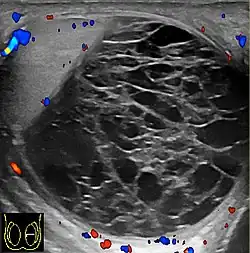

Fibrous pseudotumors, also known as fibromas are thought to be reactive, nonneoplastic lesions. They can occur at any age, about 50% of fibromas are associated with hydrocele, and 30% are associated with a history of trauma or inflammation (Akbar et al., 2003). Although the exact cause of this tumor is not completely understood, it is generally believed that these lesions represent a benign reactive proliferation of inflammatory and fibrous tissue, in response to chronic irritation. Sonographic evaluation generally shows one or more solid nodules arising from the tunica vaginalis, epididymis, spermatic cord and tunica albuginea [Fig. 18]. A hydrocele is frequently present too. The nodules may appear hypoechoic or hyperechoic, depending on the amount of collagen or fibroblast present. Acoustic shadowing may occur in the absence of calcification due to the dense collagen component of this tumor. With color Doppler sonography, a small to moderate amount of vascularity may be seen [Fig. 19].

Fig. 18. Fibrous pseudotumor. A homogeneous hypoechoic nodular lesion is seen attached to the tunica associated with minimal amount of hydrocele. -

Fig. 19. Fibrous pseudotumor. With color Doppler, a little vascular flow is seen in this fibrous pseudotumor.